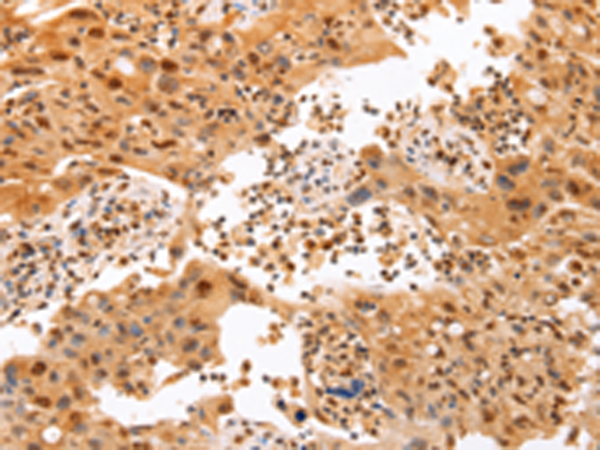

分类: 科研抗体货号: P07698别名: CMM8; OCA1A; OCAIA; SHEP3应用: WB,IHC反应种属: Human, Mouse